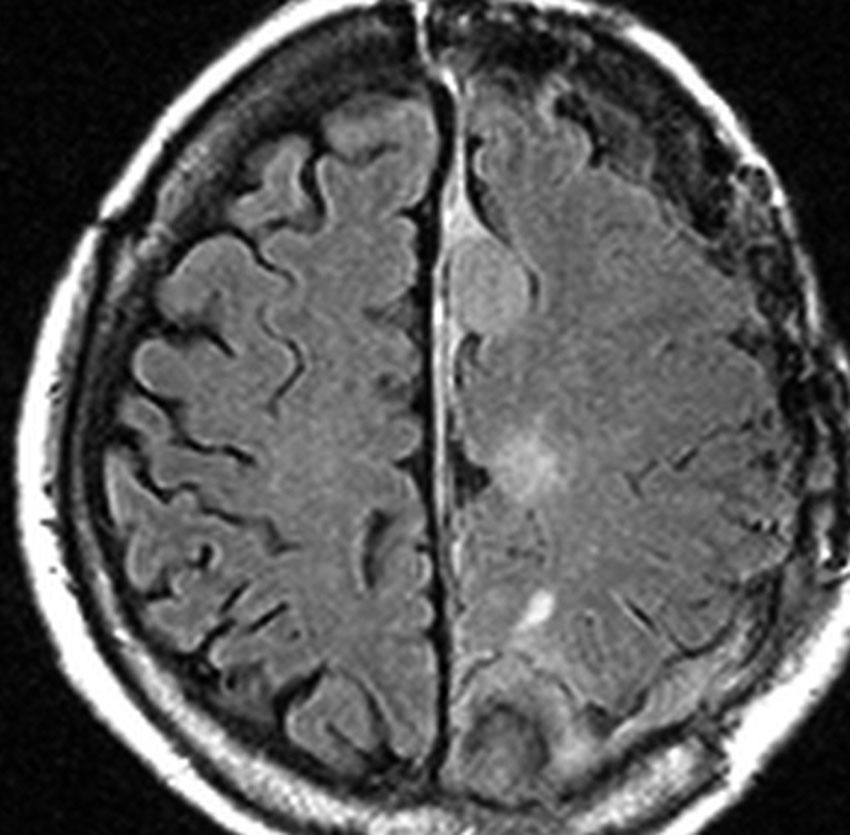

片側髄膜腫症 unilateral meningiomatosis

50歳ころから15年間に3回の開頭手術を受けている患者さんです。parasagittal, falx, convexityなど6個の髄膜腫がすでに摘出されています。左側だけ,テント上だけに髄膜腫が20個くらい多発していました。これらはグレード1で,anaplastic meningiomaの転移ではありません。

やがて蝶形骨縁の髄膜腫の増大速度が早まりatypical meningiomaとなりました。MIB-1 index が10%の高値でした。病理学的にも,psamomatous meningiomaなど様々な種類の髄膜腫が多発しています。